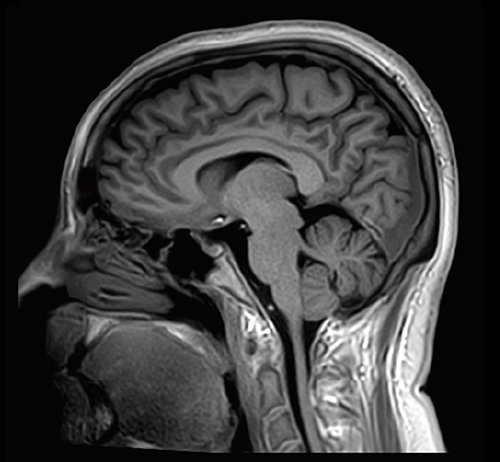

Der Vantage Galan 3T von Canon Medical Systems bietet Ihnen und Ihren Patienten eine neuartige Erfahrung in der Magnetresonanztomographie. Der Vantage Galan 3T legt sein Augenmerk auf das positive Patientenerlebnis, eine hohe Bildqualität und einfache klinische Arbeitsabläufe.

KI-optimiertes Arbeiten und modernste 3T-Technologie machen den Vantage Galan 3T von Canon Medical aus. Canons KI-Anwendung AiCE, kurz für Advanced intelligent Clear-Imagequality Engine, entfernt intelligent das Rauschen und führt zu einer Verbesserung des SNR (Signal-Rausch-Verhältnis). Mit Hilfe der Deep Learning Technologie gelingen besonders klare und deutliche Bilder. Insgesamt ermöglicht die KI-Unterstützung des Vantage Galan 3T somit nicht nur eine höhere Auflösung der Bilder, sondern verkürzt in vielen Fällen auch die Aufnahmezeit.